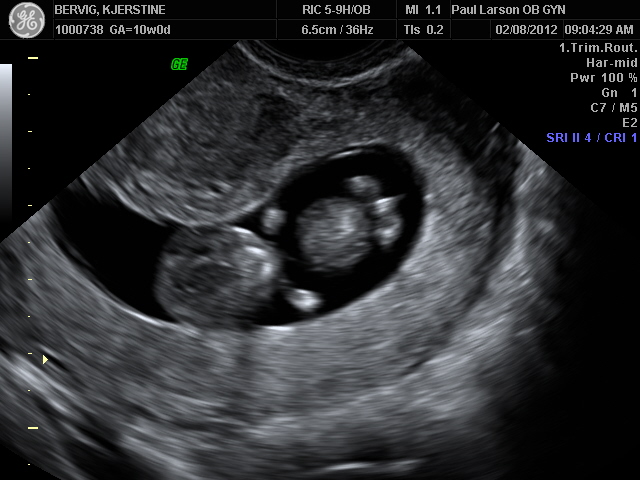

10 week ultrasound boy. Your baby’s gender is determined at the moment of conception – when the sperm contributed a Y chromosome, which creates a boy, or. It is most common that the routine ultrasound is done at weeks and many women do find out the sex of the baby then. Early 3D of twins!.

Before 10 weeks of pregnancy, the genital tuber appears to be the same in both male and female fetus’. Your Twin Babies at 10 Weeks Pregnant Your babies have only got a little bit longer, growing from an inch in week 9, to around an inch and a quarter this week. Beyond this point, noticeable anatomical differences in the genitals can show up on the scan.

Between 6 and 10 weeks. The third trimester is the most common time for patients to request the 3D/4D sonogram. Week 10 Ultrasound You'll notice in this image that your baby-to-be is looking more and more like a newborn.

Between 10 to 15 weeks, the testes begin to move out of the fetal abdomen and into the area where the boy sex organs are forming. At 10 weeks, the amniotic fluid contains other nutrients that help the baby develop. While you eagerly wait during the ultrasound, keep in mind that you may not actually get to see the baby.

The 10-week ultrasound scan is also called a dating scan, as it is used to determine the gestational age of the baby and predict the due date. Anencephaly is the absence of a major portion of the brain, skull, and scalp that occurs during embryonic development. Apr 18, 18 - How to accurately find out the gender of your baby at 9 weeks pregnant.

Ultrasound scan of 10 weeks old twin boys. It’s not always 100 percent accurate, though. But their weight has doubled, to 0.14 ounces.